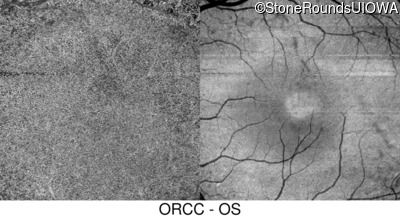

Infrared Fundus Photograph - Left - 20/32

Exemplar